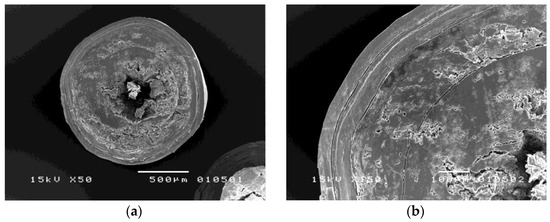

3.2.1. Morphology of Coated Metoprolol Tartrate Pellets